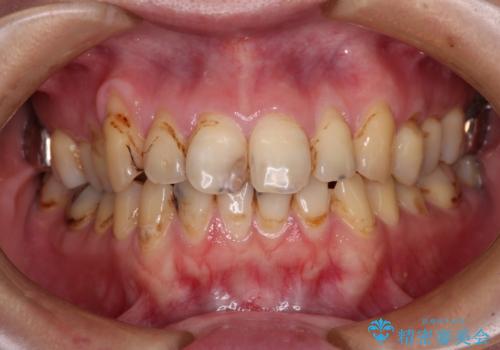

- 前歯のオールセラミック治療を検討しているとのことで来院された患者様です。

前歯は着色や虫歯治療の跡が目立っている状態で、オールセラミッククラウンによる審美治療を希望されていました。

歯肉が非常に菲薄であり、オールセラミッククラウンを装着後の近い将来歯肉退縮によりセラミックの境目が見えてくることが懸念されました。

まずは歯肉移植術により顕著に露出している歯根面を被覆して自然な歯肉ラインとし、同時に歯肉の厚みを増大させることで将来の歯肉退縮を予防することを提案しました。